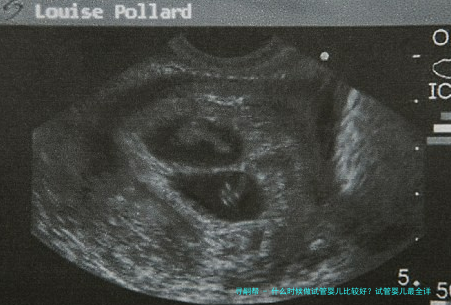

接下来要做的便是促排卵以及监测卵泡,一般来说在黄体的中期也就是月事的第二十一天的时间,就可以开始使用药物,让整个体内的促性腺激素身在一种较低的水准,用药八日左右,基本上也全部是例假来潮,如此整个例假的第3天到第7天开始做好肌肉注射,并且能够做好促卵泡的发育,三天其后的B超检测卵泡生长状况,能够有效调治所有的用药剂量。

在试管婴儿手术实施过程中,可以通过超声疏导下来做促排卵和提炼精子,在体外进行受精,培育72小时随后发育好的受精卵就可以放到胚胎当中,紧接着就能够做子宫腔的移植。如果是第3代试管婴儿的话,还需要做胚胎保存。

女方把握性超排卵,借助B超和血检监测卵泡动向生长;